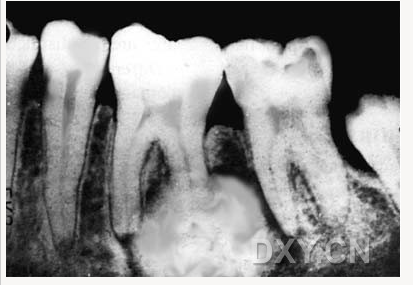

根尖囊腫

牙源性角化囊腫